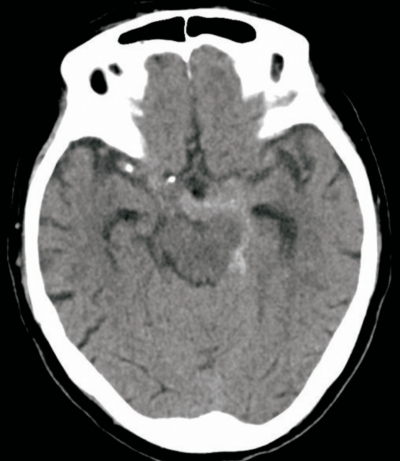

60歳の男性。突然起こった激しい後頭部痛、悪心および嘔吐を主訴に来院した。症状出現後、後頭部痛は少しやわらいだが、市販の鎮痛薬を服薬しても継続したため受診した。

来院時、意識は清明で項部硬直は認めなかった。頭部CTを別に示す。